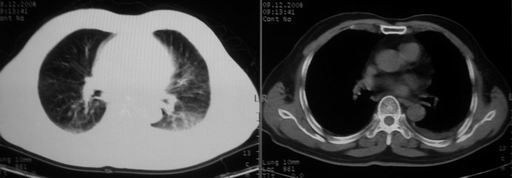

男,78岁,咳嗽、咳痰、发热入院,抗炎治疗一周后已退热,咳血似痰。

抗炎治疗一周热退,提示为炎症,现片示病灶范围增大,边缘清楚,建议继续治疗,不除外肺脓肿

炎症性病变;左侧胸腔积液。

ct左肺下叶大片状高密度影,病变密度不均,界限不清,左侧胸腔积液,治疗后复查临床症状好转而影像学表现病变有发展,还是首先考虑感染性病变,复查时间短附合感染性病变的病理改变。